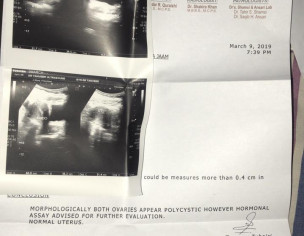

Edit. Asking for Self, Female, 21 years old, Karachi I have been feeling lethargic or rather too much distressed since the past couple of days on and off, i’m under no such stress, feel like the heart is sinking specially at night time and heaviness in the arms sp upper arms, around shoulders and specially palms and fingers and legs and somtimes too much tingling like pressure too as if its from within the veins. I have pcos. Have irregular menstrual almost evertime. cycle which exceeds 7 days sometimes if the hormones are acting up. Has happened once before last year that the discharge/bleeding continued for 20 days and this time around experiencing the same currently its the 10th day that it hasnt ended (its on and off with no bleeding to very very light once good flow too.). I’m attaching previous reports. Need expert advice. Thanks